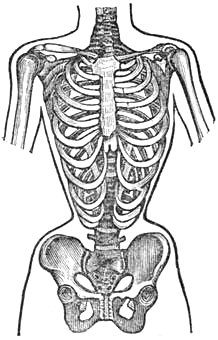

| 250. | HOW WASP WAISTS ARE MADE, | 799 |

| 251. | A CONSUMPTIVE WAIST, | 800 |

| 252. | NON-CONSUMPTIVE WAIST, | 800 |